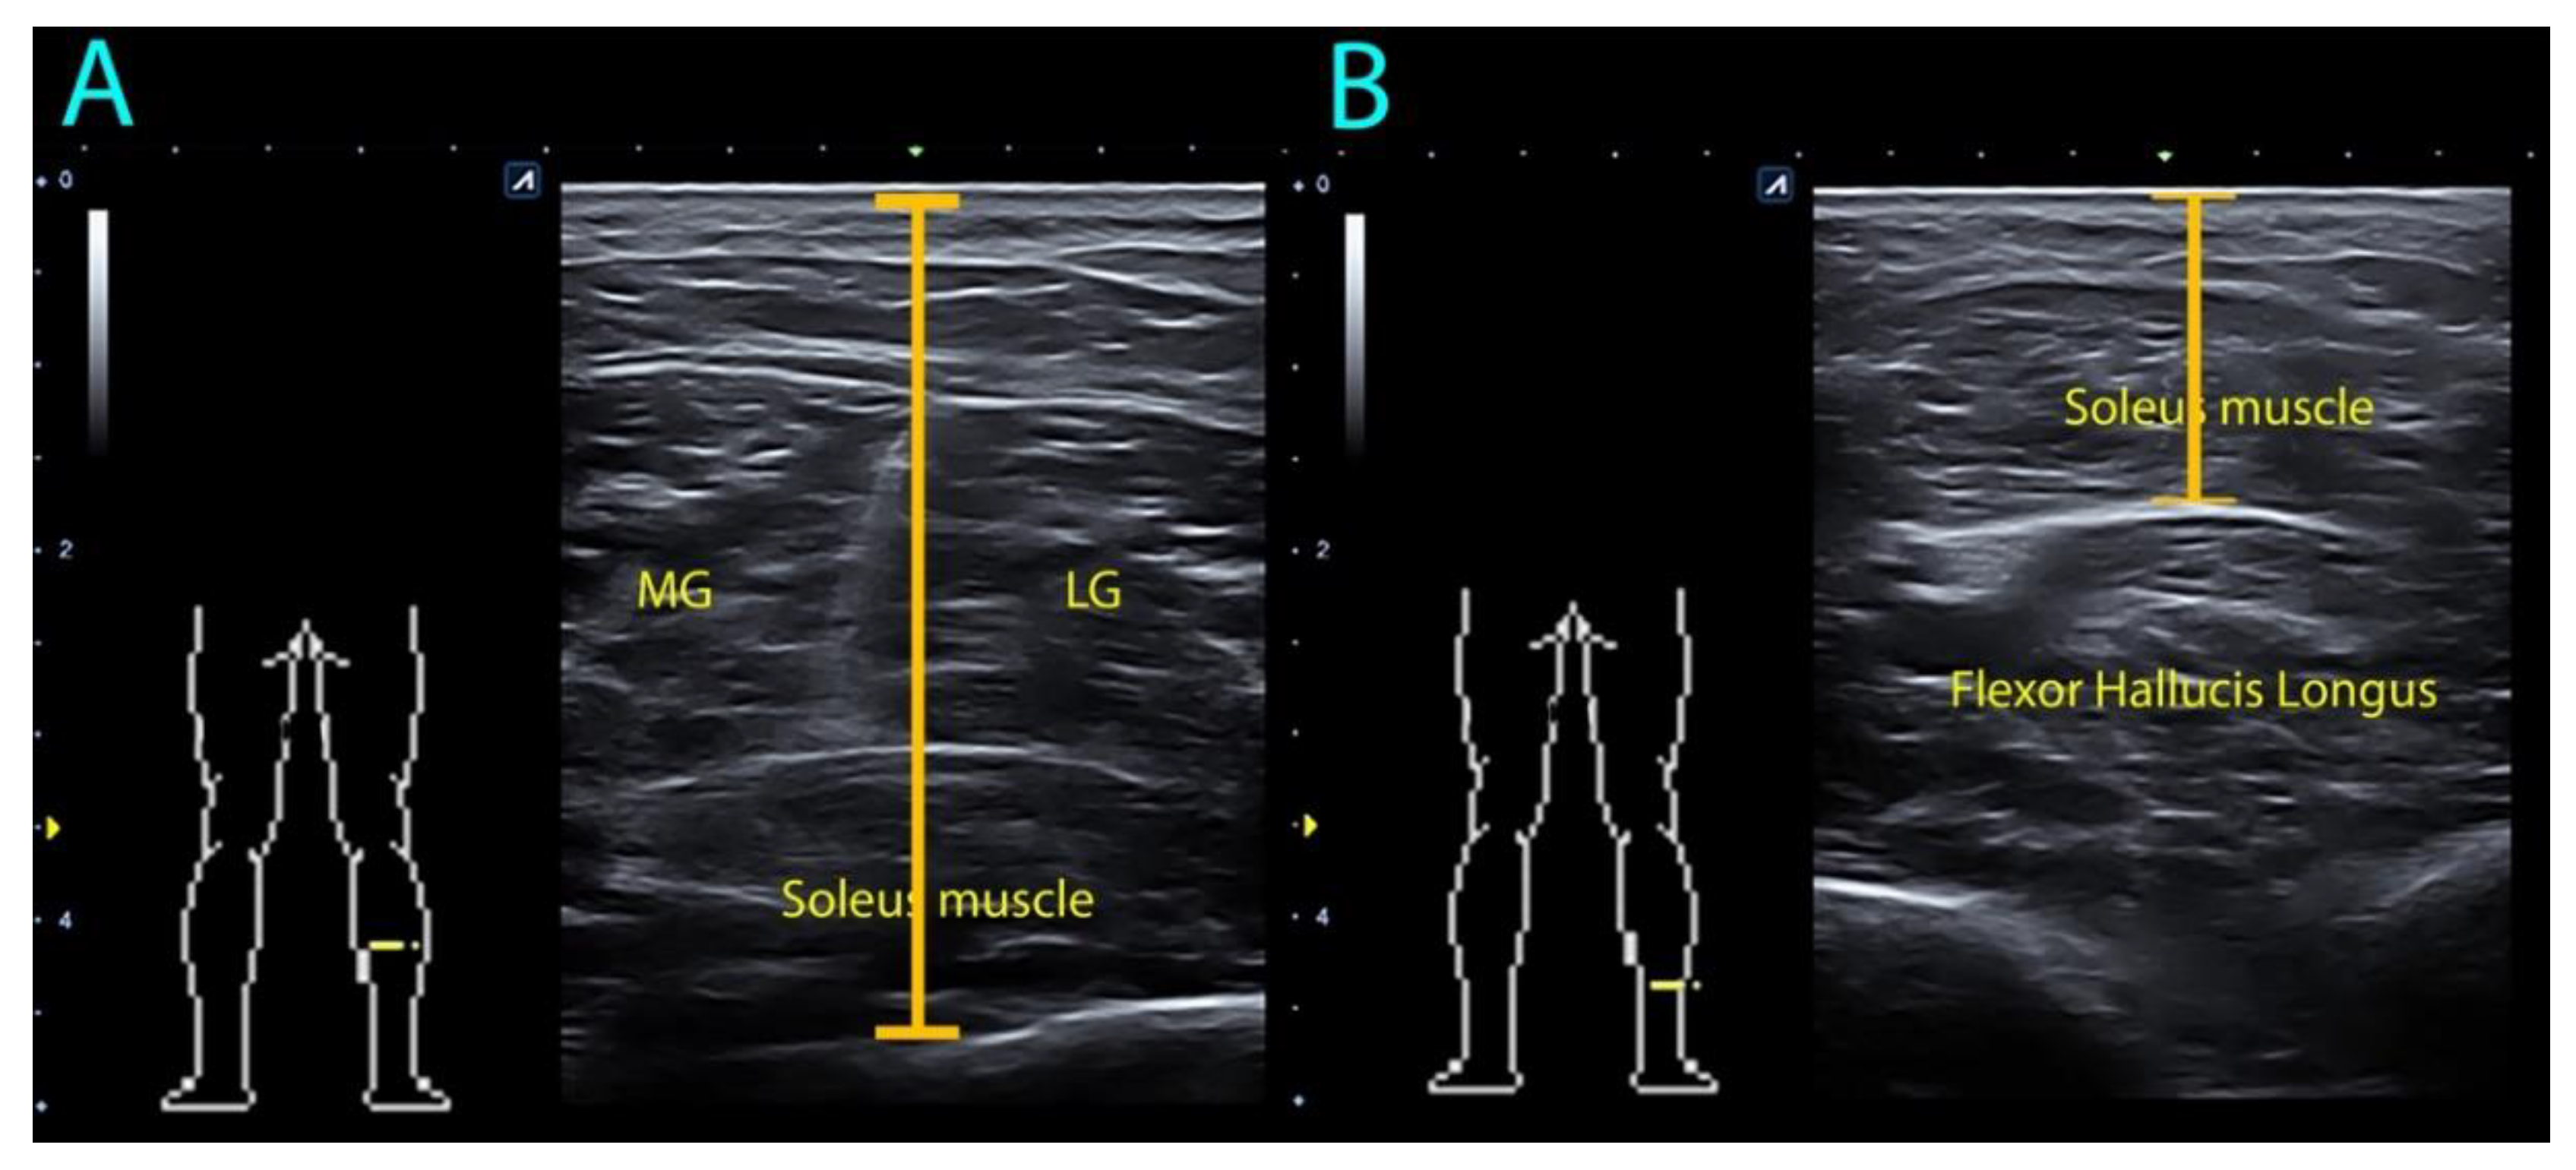

2.3. Soleus Ultrasound Procedure